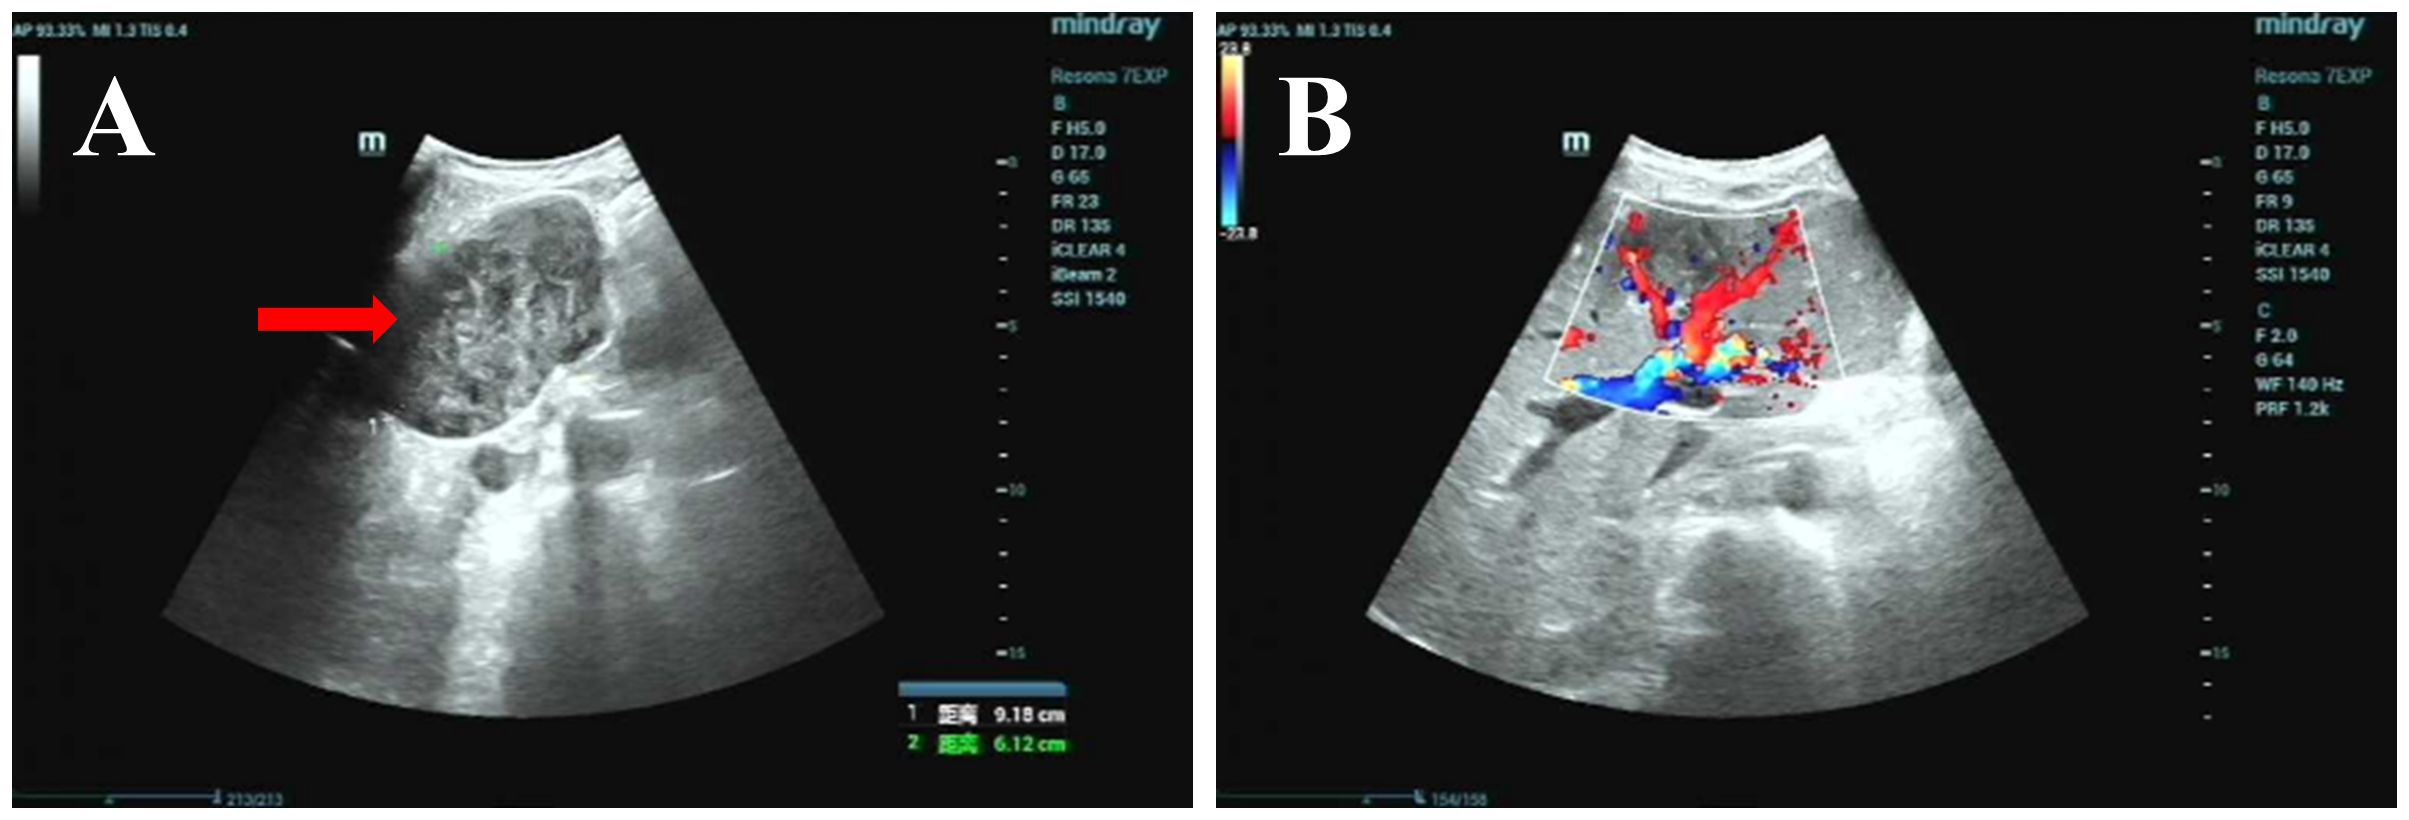

Background: Primary hepatic leiomyosarcoma (PHL) is an extremely rare malignancy often misdiagnosed due to nonspecific imaging features overlapping with cholangiocarcinoma. This case highlights diagnostic challenges and the potential association of SDHB positivity with PHL prognosis. Case Presentation: A middle-aged male presented with an asymptomatic liver mass. Preoperative CT/MRI revealed a 10-cm lesion with progressive heterogeneous enhancement and delayed capsular enhancement, initially diagnosed as cholangiocarcinoma. Left hepatic lobectomy confirmed PHL. Immunohistochemistry showed SDHB positivity and low Ki67 (15%). The patient recovered well with no recurrence at 6-month follow-up. Conclusions: PHL can radiologically mimic cholangiocarcinoma, necessitating inclusion in differential diagnoses for "cholangiocarcinoma-like" liver masses. SDHB positivity may indicate favorable tumor biology, but further studies are needed to validate its prognostic value. Surgical resection remains curative for localized PHL.